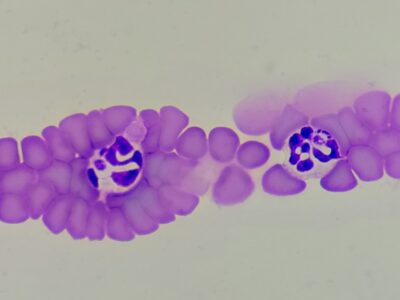

anaplasma inclusions

anaplasma inclusions -

anaplasma inclusions

anaplasma inclusions -